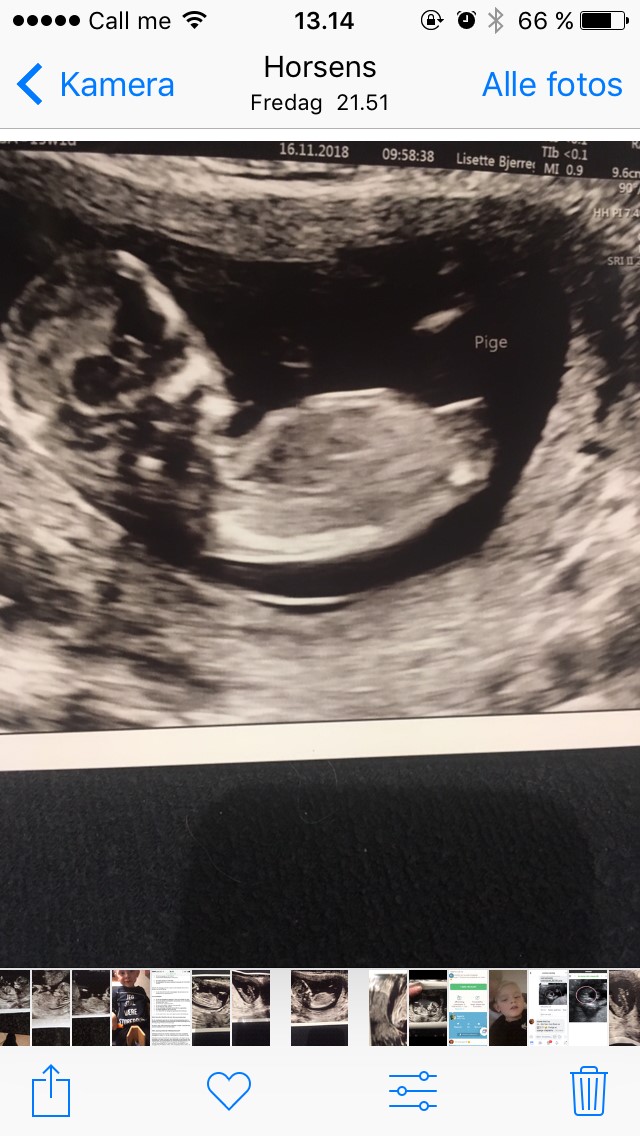

Pige!!

men jeg føler mig vildt usikker. Scannings damen sagde at hun var 100% sikker...

er i enige ?

Da vi blev scannet var der en tydelig tap når hun scannede mellem benene. Jeg havde set det var en dreng inden hun fortalte det. På dit billede hvor man kan se mellem benene synes jeg det ligner en pige.

På billederne hvor man ser baby fra siden, kan jeg ikke vurdere om det er en pige eller dreng. Jeg kan godt se hvad du synes ligner en tap, men jeg tror scanningsdamen har styr på det - med mindre du har valgt en tidlig kønsscanning. Folk der bliver scannet i uge 16 bliver af og til snydt.

Altså det ligner fuldstændigt de billeder jeg har fået og der sagde hun også hun var 100% sikker på det var en pige, så det har ds bare at være rigtig, su kan jo også se der ingen tap er nogle steder. Hvorfor få lavet en kønsscanning hvis du alligevel ikke stoler helt på den?

Det ligner en pige

Det ligner rigtig meget de billeder vi også fik og vores PIGE er nu knap 4 måneder